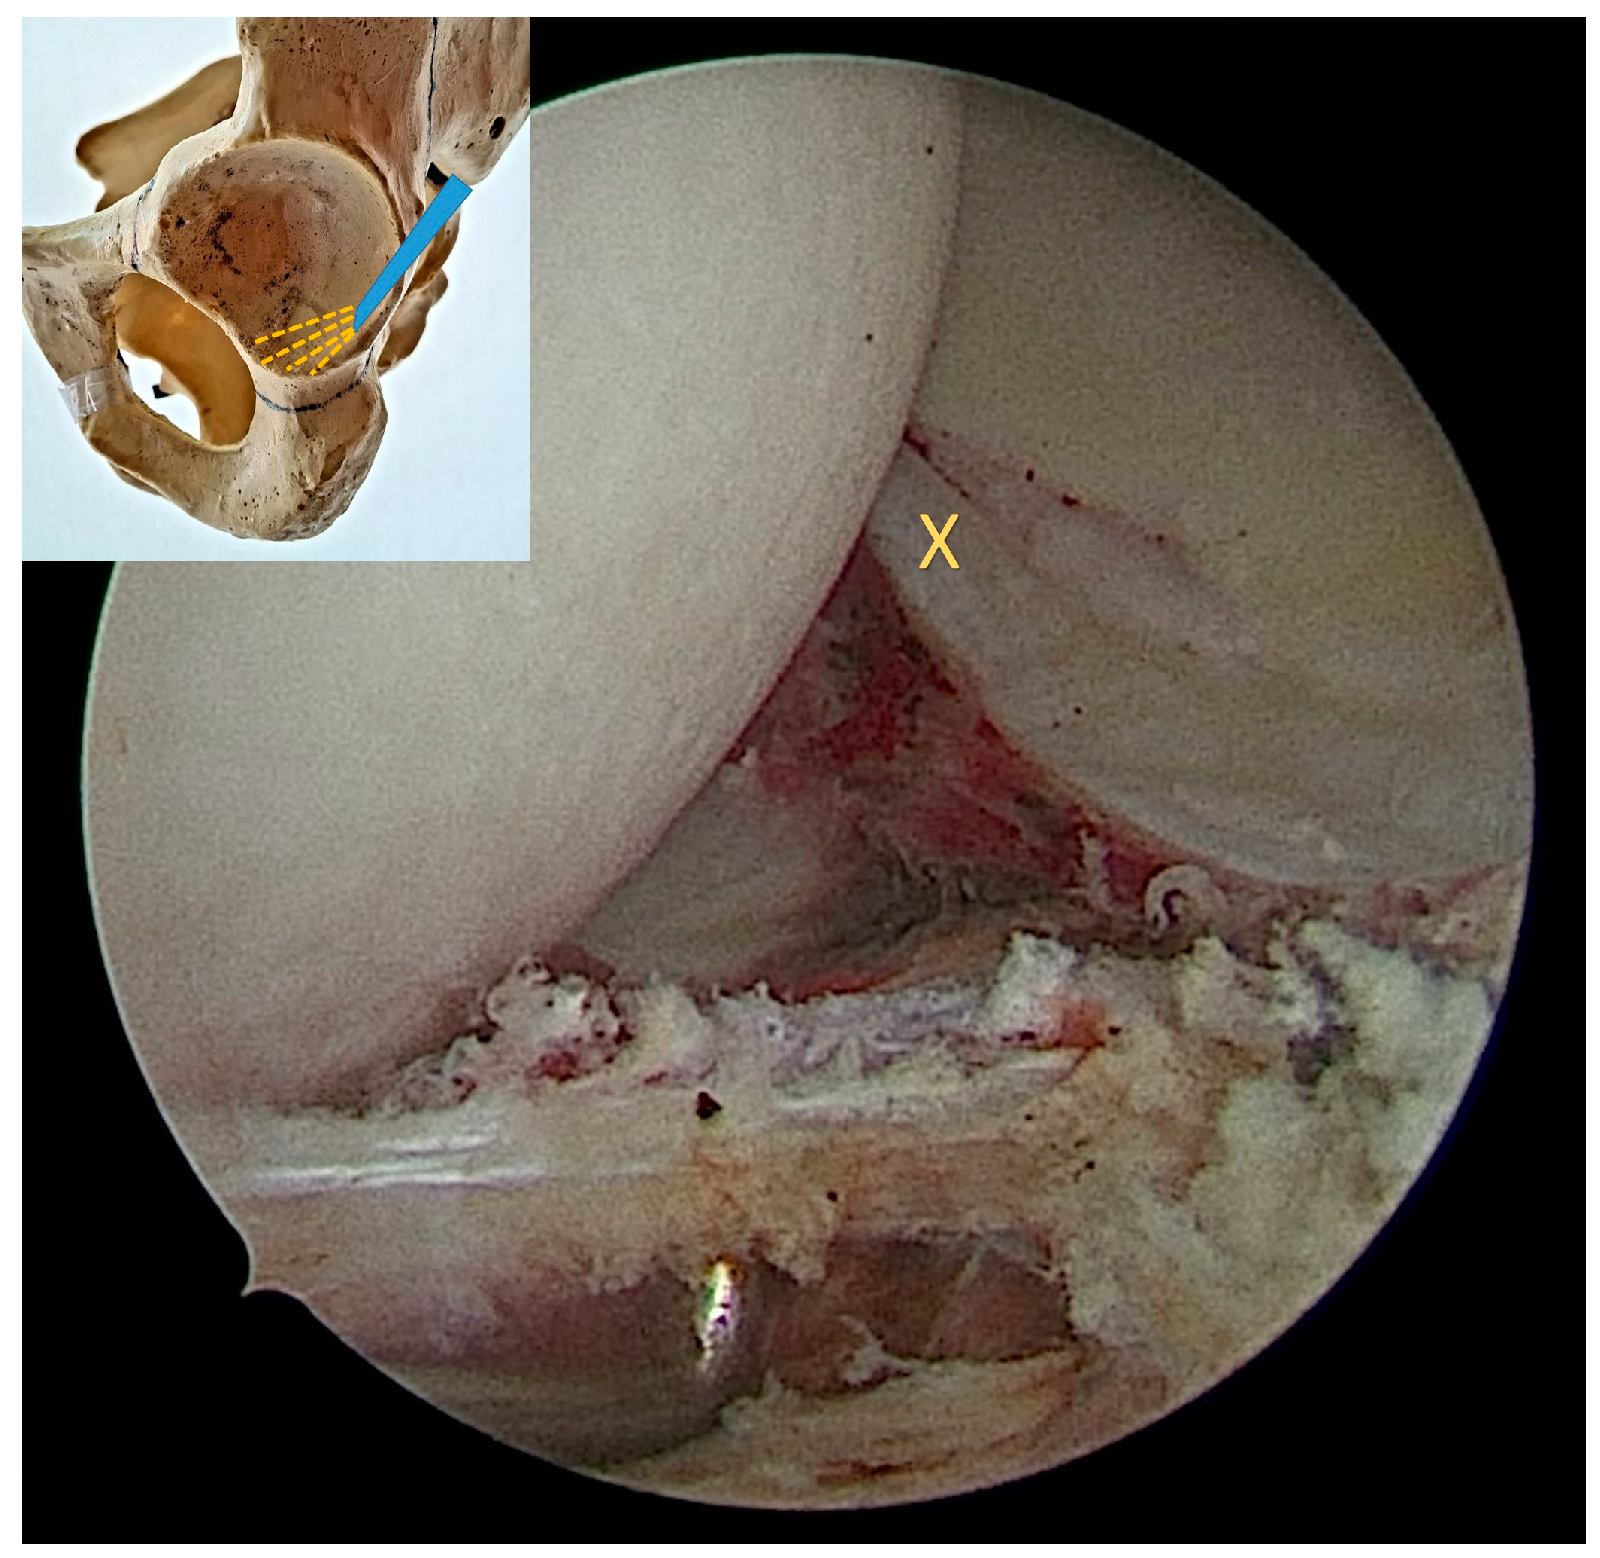

2.2. Surgical Procedure